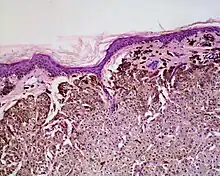

Balloon cell nevus is a benign nevus.[1] It appears like a melanocytic nevus.[2]

Histologically it is characterized by swollen, pale, polyhedral melanocytes, with pale cytoplasm and a central nucleus.[2] It is different to balloon cell melanoma,[3] which has larger nuclei and is structured like a melanoma.[1]